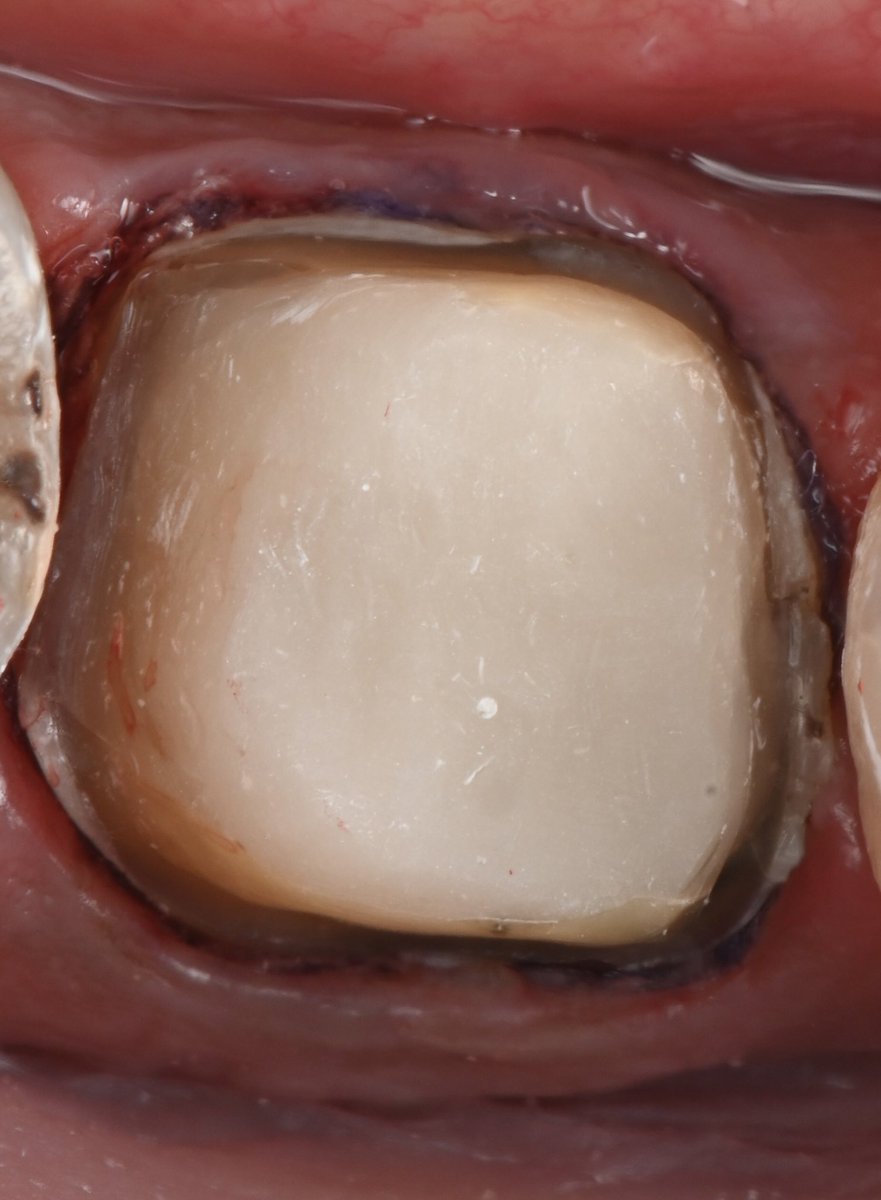

نعم هذه الصوره قبل وبعد ولكن..... شوفو معي خطوة بخطوة كيف قدرنا نحافظ على هذا السن🦷❤️